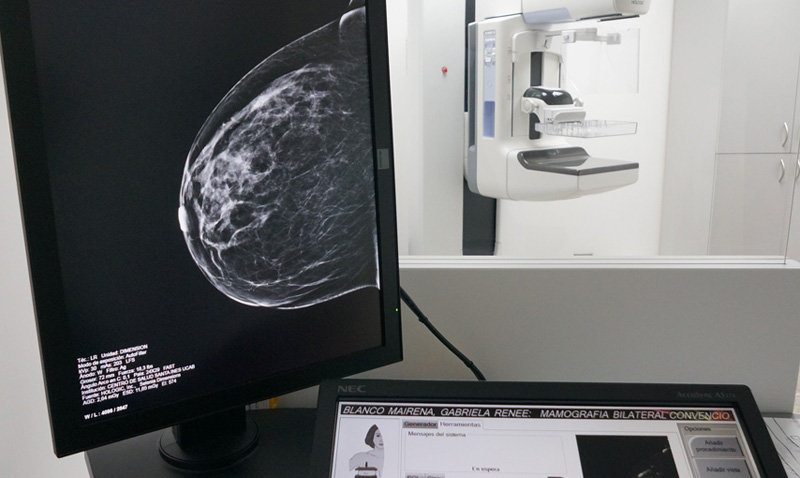

El mamógrafo digital del Centro de Salud Santa Inés UCAB (CSSI), cuyo servicio fue modernizado en noviembre de 2014, tiene la capacidad de elaborar tomosíntesis, un examen diagnóstico en imágenes para despistaje de cáncer de mama y otros padecimientos mastológicos.

La tomosíntesis, básicamente, fusiona la conocida mamografía bidimensional y la tomografía, lo que genera imágenes con cortes milimétricos del tejido mamario. Tal y como lo afirma la doctora Xiomara Cabello, especialista en mastología del CSSI, este examen brinda una imagen más clara, con mayor precisión y calidad, ya que el experto puede analizar el resultado, corte por corte, para determinar la ubicación, tamaño y extensión de cualquier patología o lesión. Asimismo, permite vislumbrar lesiones muy pequeñas, como microcalcificaciones, las cuales generalmente quedan ocultas al realizarse mamografías digitales.

Como en todo examen de diagnóstico por imagen, se utiliza radiación para realizar el estudio; Lilibeth Rodríguez, técnico encargada de operar el mamógrafo, confirma que esta prueba utiliza un poco más de radiación que la mamografía digital; sin embargo, es igual de inocua. La tomosíntesis es recomendada para mujeres con tejido fibroglandular denso, ya que permite un estudio más detallado de las mamas.

En el área de imagenología del CSSI se presta este servicio de diagnóstico; además, se ofrece un paquete que incluye la tomosíntesis, una mamografía 3D y una bidimensional. Todos estos exámenes se realizan con una misma compresión del seno en el mamógrafo, utilizando solo un disparo del equipo; contrario a los que hacía anteriormente, cuando se sometía a la paciente a varias compresiones mamarias en diferentes ángulos.